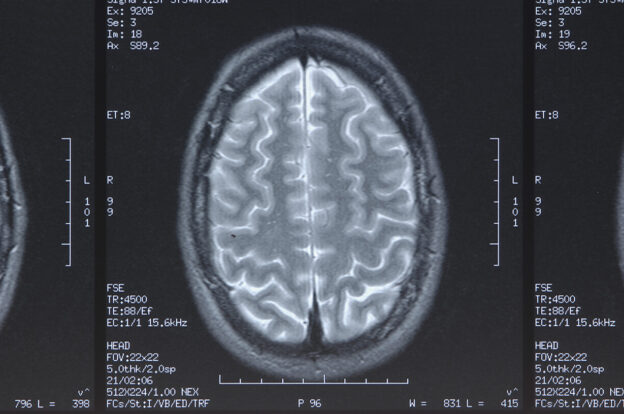

Escrito por Dr. Vithor Ely Bortolin da Silva| Revisado por Dra. Jessica Caetano Barbosa A hemorragia subaracnóidea aneurismática (HSA) é responsável por aproximadamente 5% de todos os acidentes vasculares cerebrais e está associada a taxas de morbidade e mortalidade de até 60%. Esses pacientes apresentam uma variação considerável em seu curso clínico e resultado funcional, o que é explicado principalmente pela gravidade do sangramento inicial causando lesão cerebral precoce, bem como complicações secundárias, como ressangramento, isquemia cerebral tardia ou hidrocefalia. A predição adequada de complicações e resultado funcional é de suma importância para o manejo da doença e aconselhamento de pacientes e familiares. Com esse intuito o escore HATCH, que varia de 0 a 13, compreende 6 preditores independentes e deve ser calculado logo após o tratamento do aneurisma: hemorragia, idade, tratamento, estado de admissão clínica medido pelo WFNS e hidrocefalia (ver Tabela 1). PreditorValorHemorragiaHSA não visível1HSA < 15mm1HSA >15mm2Ressangramento3Idade> 60 anos1TratamentoCoil0Clipe2WFNS1 ou 203 ou 4253HidrocefaliaPresente2Total1 a 13 O estudo avaliou 701 pacientes, sendo 526 mulheres, com a faixa etária média de 55 ± 13 anos. Com uma curva ROC de 0,81 (IC 95% 0,77-0,84), o escore HATCH mostrou capacidade discriminativa superior para detectar resultados desfavoráveis no acompanhamento, principalmente nos pacientes com…...